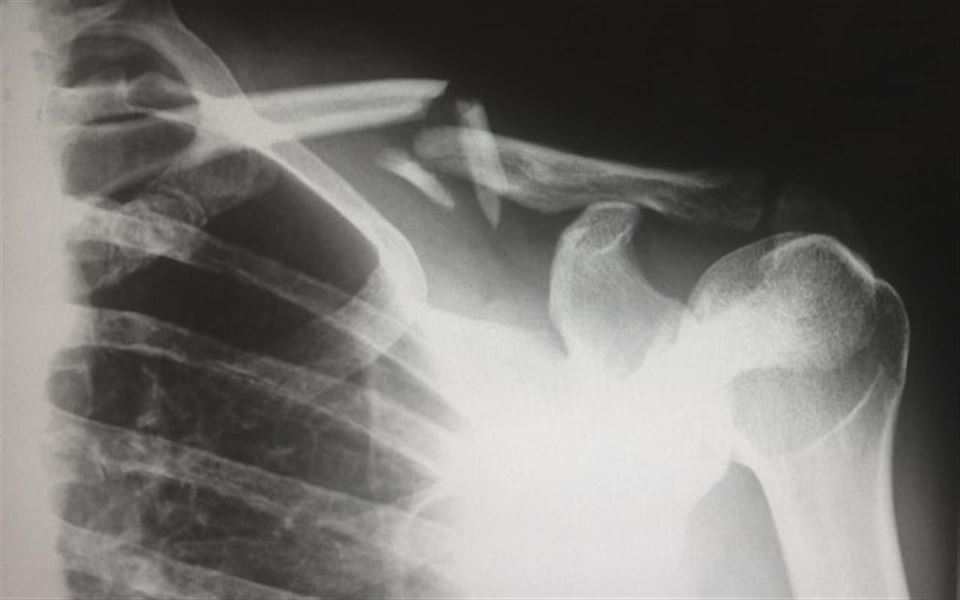

En frossen skulder, også kendt som "frossen skulder" eller adhæsiv kapsulitis, er en tilstand, der ofte forårsager smerte og nedsat bevægelighed i skulderen. Det opstår, når bindevævet omkring skulderleddet bliver tykt og stramt, hvilket resulterer i begrænsning af bevægelse og ømhed. Hvis du har oplevet noget lignende så hop ind på siden og læs mere omkring frossen skulder øvelser.

De mest almindelige symptomer på en frossen skulder inkluderer smerter og stivhed i skulderen, hvilket gør det vanskeligt at udføre selv simple bevægelser som at løfte armen eller dreje skulderen. Disse symptomer kan gradvist forværres over tid og forårsage betydelig ubehag.